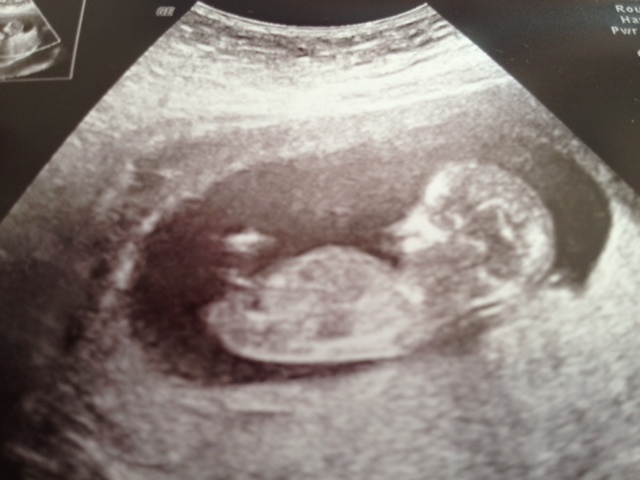

These are our 3 shots from our 12 week 4 day scan any predictions on Nub or Skull Theory Please?